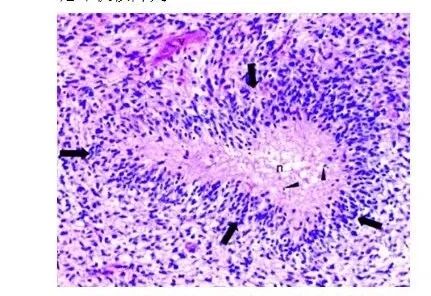

怎么买病理图文这些影像征象背后的病理基础,今天才知道!_https://www.jmylbn.com_新闻资讯_第8张

病理学家在检查某些肿瘤的显微镜下,注意到细长的细胞核排列整齐,并根据它们与这些强化物的相似性,附加了描述性的术语“栅栏”。当核栅栏反映出细胞核发展出这种独特的生长模式的自然趋势时,它们可被视为”原生”; 当核栅栏排列形成对坏死等外部影响的反应时,它们可被视为”次生”。

胶质母细胞瘤呈节律性栅栏样改变(肿瘤细胞核线性波),这个是胶质母细胞瘤原生的生长方式之一,不具特异性,类似的还有神经鞘瘤、室管膜瘤、脑膜瘤等。